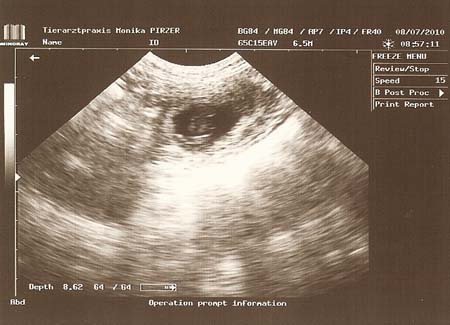

Heute war wieder ein spannender Tag. Shiva war mit uns beim Ultraschall. Und wir freuen uns nun riesig darüber, dass Shiva sichtbar aufgenommen hat. Somit kommen wir unsererm B-Wurf wieder ein Stück näher. Wenn alles stimmt, dann erwarten wir so um den 11. August Nachwuchs :-).